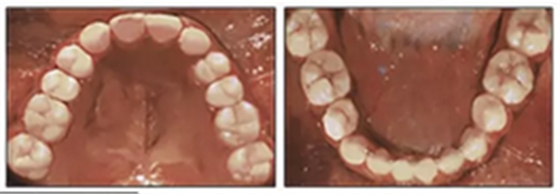

經(jīng)過24個(gè)月的保持后,咬合保持得很好(圖11 ; 圖12)。在上牙弓中,應(yīng)用固定舌側(cè)保持器以防止任何復(fù)發(fā)傾向。在下牙弓中,治療后拔除第三磨牙。